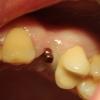

Andex Опубликовано 20 октября, 2012 Поделиться Опубликовано 20 октября, 2012 (изменено) В поддержании темы про применение мини-имплантов, хотел бы поделиться своим опытом. Прошу заранее прощения за качество фотографий - когда все в одном лице и врач и ассистент и медсестра и фотограф - тяжело сделать качественнее. Буду благодарен за конструктивные замечания и советы. 1) Имплантация 31 зуба. Ширина кости в медиодистальном размере- 2,8 мм, в вестибулооральном - 2,7. Имплант d 1.8 - L 13. Ниже файлы по порядку - оптг, прицельный рентген и живое фото 2) Имплантация 24 зуба. Имплант d 2.4 - L 10. Кости хватило бы и под двухэтапный. Файлы по порядку - живое фото, снимок с физиографа в перевернутом виде(так датчик развернулся) 3) Имплантация 46 зуба на двух мини-имплантах d 2.2 - L10. Восьмой удалять пациента не дался, поэтому начали лечение хотя бы с восстановления 46 зуба. Файлы - оптг, прицельный рентген, живое фото, рабочая модель, вид внутренней части коронки. Изменено 20 октября, 2012 пользователем Andex Ссылка на комментарий